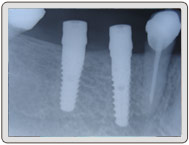

植入植體

治療後